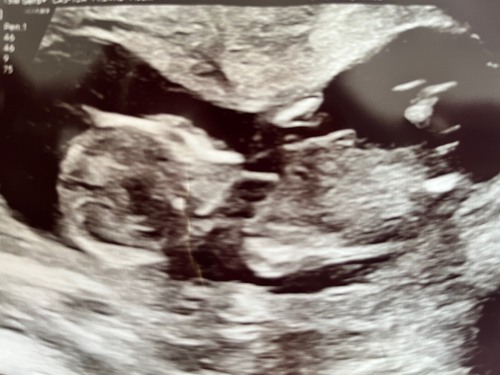

Wat denken jullie jongen of meisje?

Zie mijn bericht, begin van dit topic